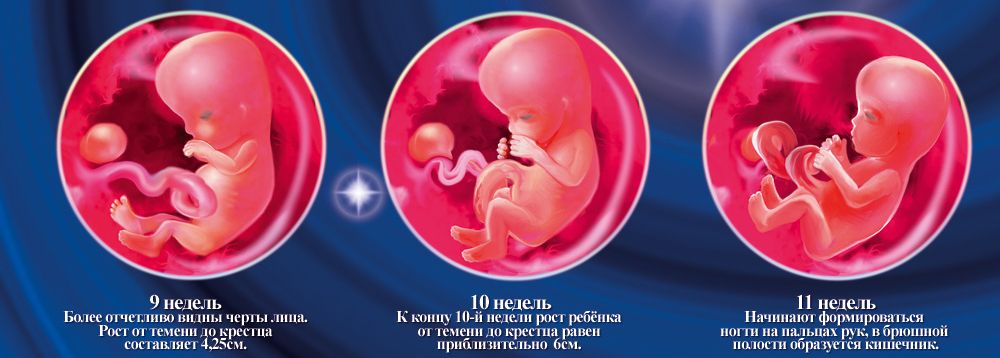

Развитие зародыша на 12 неделе: визуальный обзор